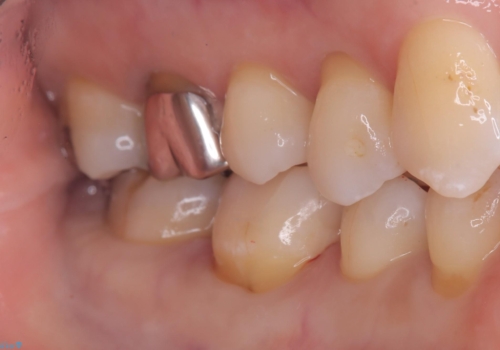

- 主訴:右下6番目と7番目の歯の間に食べかすがしょっちゅう詰まる

コンタクトの再現と歯冠色補綴物へのやり替えを目的とし、セラミックインレーでの治療となりました。

歯間に食渣がつまるのをどうにかしたいとの主訴のもと、治療を開始しました。フロスを通してみると、コンタクトは無く0.25mm程のスペースがありました。

メタルインレーを歯冠色のものに変えたいという希望もあったため、セラミックインレーでのやり替えによるコンタクトの再現をしています。